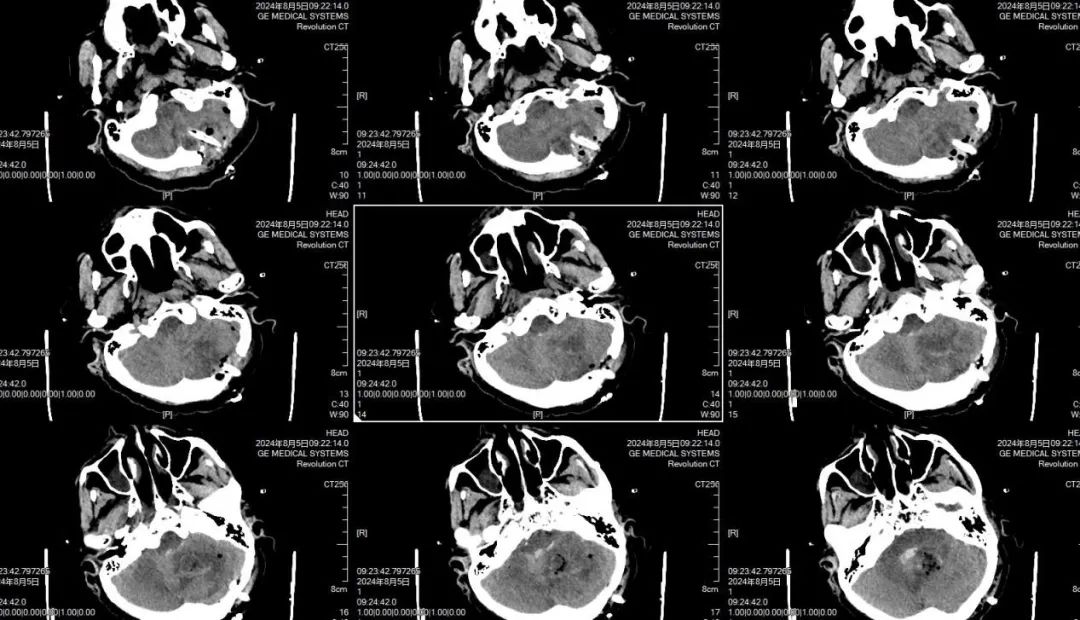

郑维超主任与黄佳荣医生认真听取了家属对病情的详细介绍后,以极其严谨、科学的态度对病情进行分析诊断。他们深知,小脑出血位置特殊,稍有不慎便会危及患者生命。但考虑到患者目前已陷入昏迷状态,为了更加准确地掌握病情变化,他们果断决定对患者再进行一次 CT 检查。11 点 53 分,头部 CT 复查结果显示,小脑出血较之前明显增多,并且伴有急性脑积水。患者病情万分危急,生命危在旦夕,每一秒的拖延都可能带来不可挽回的后果。郑维超主任立即会同神经外科专家组,展开了一场紧张而激烈的病情讨论。凭借着丰富的临床经验和专业知识,迅速制定出一套严谨周密的救治方案。经过深思熟虑,郑维超主任决定立即对重症患者依次进行脑室外引流手术、小脑血肿清除手术以及后颅窝骨瓣减压手术。

凌晨4时,当刘先生看到母亲面容安稳平和的被推出手术室,他的泪水再次夺眶而出,他双手合十,一次又一次地表达着内心深处的感恩之情。患者术后4小时,再次进行头部 CT 复查,结果显示脑室大小已恢复正常,小脑血肿被清理得极为干净。刘先生面向在手术室参与抢救他老母亲生命的全体医务人员,竖起大拇指,微微点头,以无声的方式传达着内心的感激与敬佩之意。